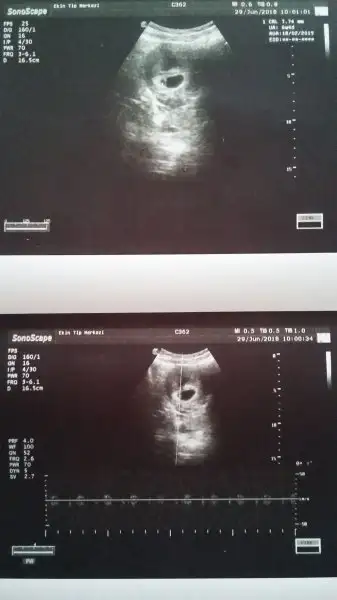

Kızlar heyet raporu nasıl alabiliriz benim hiç dermanım Yok doktora da açık açık nasıl denir progestan beni mahvetti

canım heyet için 3 doktor imzası lazım, doktorun muhtemelen 10 günlük rapor verebilir ama. progestan cidden sersemleten bir şey.